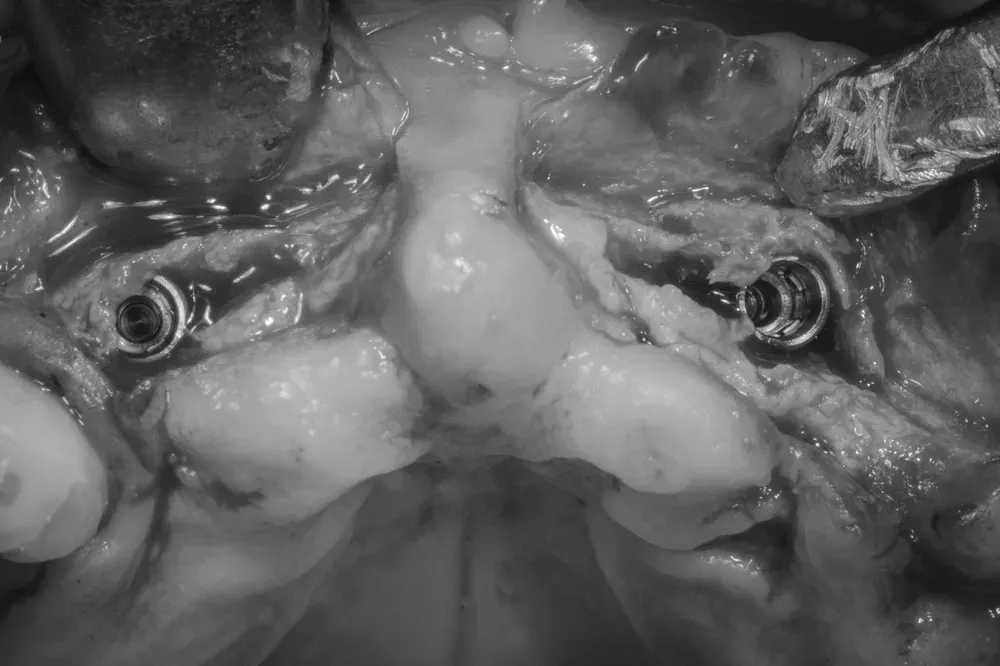

L’immagine mostra l’espansione osteo-mucosa con l’inserimento di due impianti nella pre-maxilla, in posizione 1.2 e 2.2.

Lo spazio lasciato vuoto guarirà con formazione di nuovo osso e mucosa cheratinizzata.